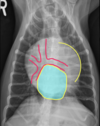

Which structures are outlined in this image?

A

dark blue: left atrium

pink: left ventricle

yellow arrow: sulcus at the junction of left atrium and left ventricle